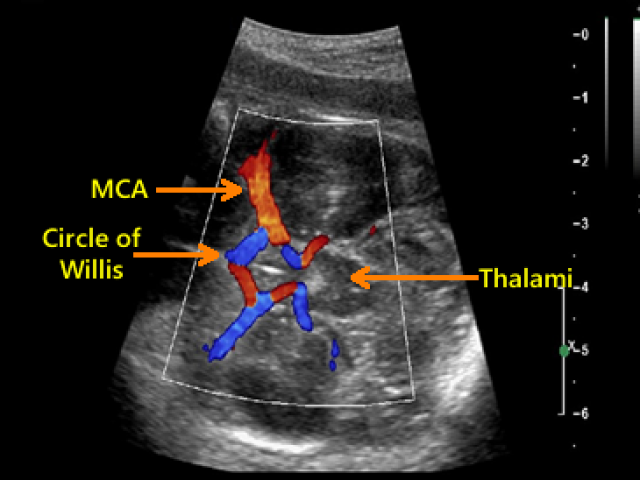

Middle Cerebral Artery, Major Malformations, Fetal Pelvis (9 CMES) $13.49 Click Here